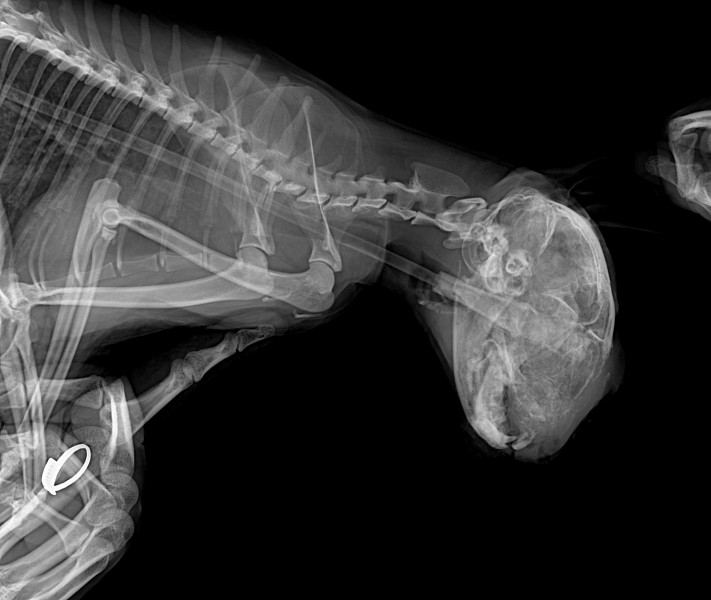

В связи с этим ревизию, чтобы понять из за чего отёк зубной врач провести не смогла, но сделала ренген: (По ренгенологическим снимкам визуализируется изменения структуры костной ткани и височно-нижнечелюстного сустава слева)

Направили на КТ, а после на консультацию онколога.

24 октября КТ.

Т.к интубация невозможна делать КТ было рискованно, однако выбора не было, КТ удалось сделать. Кости черепа целы.

Но самое главное, что сейчас сделали ренген и уже начался активный лизис костей черепа, чего не было во время КТ.